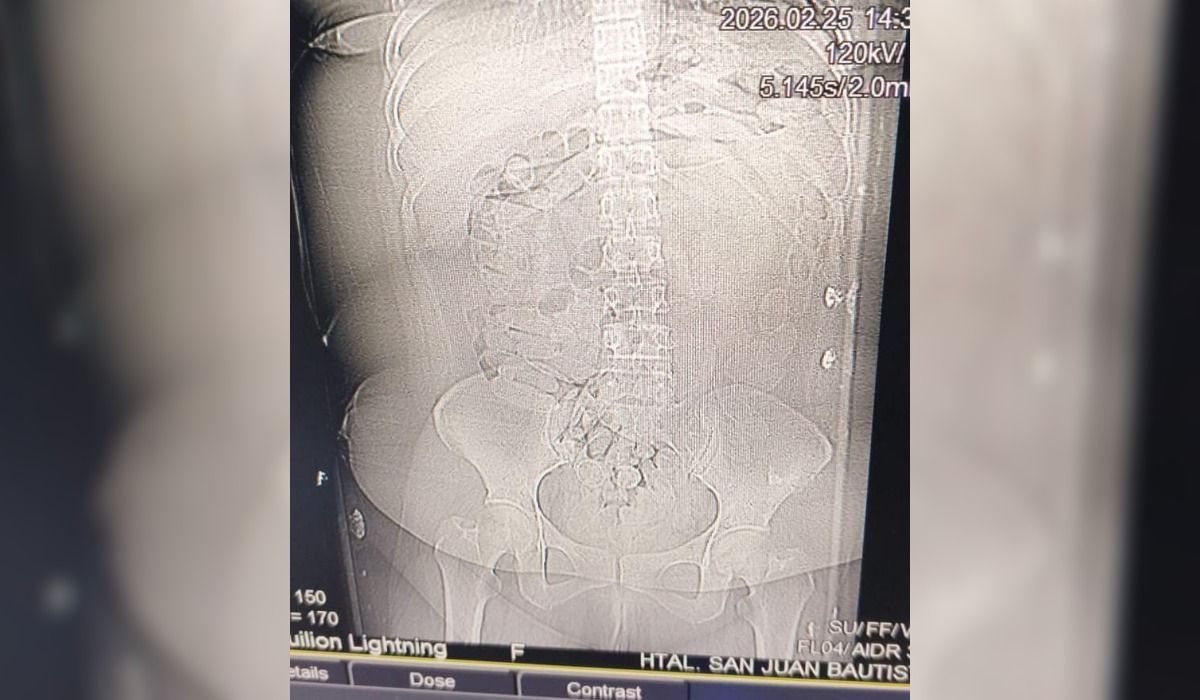

De acuerdo a lo informado por fuentes oficiales, al momento en que inspeccionaron un transporte de pasajeros con el itinerario La Quiaca (Jujuy) – Mendoza, los gendarmes detectaron a una ciudadana extranjera que presentaba indicios compatibles con el traslado de estupefacientes mediante la modalidad conocida como “camello”, por lo que se dispuso su traslado al Hospital San Juan Bautista de la ciudad de Catamarca para una evaluación médica.

Tras los estudios correspondientes, se constató la presencia de cuerpos extraños en la zona abdominal y en la cavidad genital. Como resultado del seguimiento médico, se confirmó la evacuación de 90 cápsulas.

image

La sustancia contenida en los envoltorios era de color blancuzco y, al ser sometida a la prueba de campo Narcotest, arrojó resultado positivo para cocaína, con un peso total de 1 kilo 069 gramos.